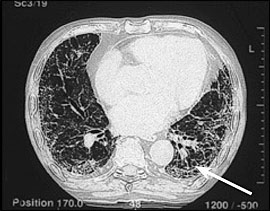

figure1

ひどい石綿症を示している胸のコンピュータ断層。

石綿症は線維性肺疾患または塵肺であり、アスベスト線維の吸入から生じる。多くの患者において、それは通常比較的マイナーな徴候をもたらす、非常に程度が軽くて痛みのない線維症によるのが特徴である。一般にアスベスト曝露のピーク時と診断の間の潜伏期間は、20〜30年である。身体検査に関する聴診音と関連する労作性呼吸困難に対する病訴は、更なる検査をすべきであるということ示している。肺機能の初めの変化は、減少した拡散能力と労作性の酸素不飽和化であるかもしれない。検査におけるプロセスがより先進になるにつれて、肺機能テストは減少した総肺気量と肺活量で制限的なパターンを明らかにするだろう。また胸部X線撮影は、一般的に増加した間質陰影としばしば胸膜プラークを示す。主にベースとして、胸の高解像度CTにおける典型的な検査結果は増加した間質陰影を含む。後に蜂窩が明らかになるかもしれない。(figure1)多くの点で、石綿症は特発性肺線維症と臨床的に類似している。しかし、石綿症は通常ゆっくり進行するが、特発性肺線維症は急速に進行する場合がある。現在の治療では、効果的に石綿症の疾患過程を変えることはできない。患者はインフルエンザと肺炎球菌のワクチンから利益を得る。かなりの職業的なアスベスト曝露と典型的な高度解像度CT検査結果歴があれば、外科的肺生検は診断を確立するためにあまり必要とはされない。外科的肺生検が行われた患者等に対して、病理学パターンでは間質性肺炎という診断なのである。これは特発性肺線維症患者に起こっている病理と同じであって、コラーゲン血管疾患(例えば慢性関節リウマチ)に伴う肺線維症でも見られるかもしれない。アスベスト小体は組織の特別な鉄の染色によって特定され、これらアスベスト小体の数は、線維症のひどさと相関する。肺組織におけるアスベスト小体の存在は、石綿症の診断を確かなものとする。